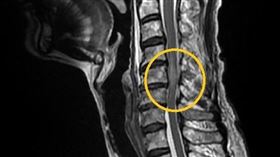

他雙腳無力險癱瘓!醫一看竟腫瘤壓迫脊髓

新北市一名60多歲男性,原本行動正常,近期卻開始出現...

手麻無力?醫示警:可能是頸椎病變的警訊

50歲的王先生,雙手麻、無力長達兩個月,近一個月症狀...

走路無力像走在棉花上?當心頸椎狹窄

常聽到病人主訴走路像是走在棉花上,沒有「腳踏實地」的...